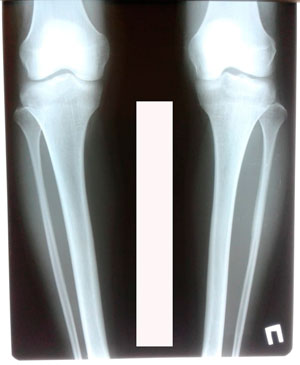

Пациентка - 23 года. Бишкек.

Дата операции - 29.01.2020

Варусная деформация голеней

Ротация справа.